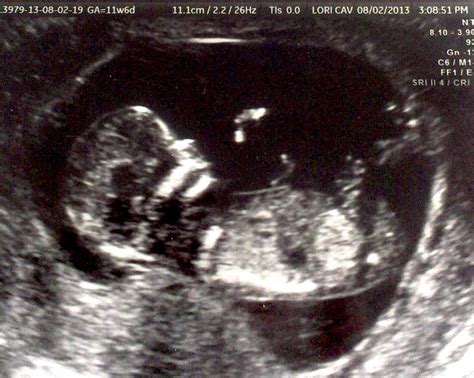

A 13 Weeks Ultrasound is a routine prenatal check-up that uses high-frequency sound waves to create images of the fetus and the uterus. This scan is crucial for several reasons, including assessing the fetus's development, detecting any potential issues, and providing a clearer picture of the pregnancy timeline.

• Fetal Development Assessment: At 13 weeks, the fetus undergoes significant developmental changes. The ultrasound can confirm the fetus's age, measure the crown-rump length (CRL), and check for the presence of key structures like the heart, brain, and limbs.

• Nuchal Translucency Screening: This scan is often combined with a nuchal translucency (NT) screening, which measures the fluid-filled space at the back of the fetus's neck. This measurement, along with maternal blood tests, can help assess the risk of chromosomal abnormalities such as Down syndrome.

• Crown-Rump Length (CRL): This measurement helps determine the fetus's gestational age and overall growth.

• Nuchal Translucency (NT) Measurement: This screening assesses the risk of chromosomal abnormalities. A thicker NT measurement may indicate a higher risk, but further testing is usually required for confirmation.

• Fetal Anatomy: The ultrasound will check for the presence of key structures, such as the heart, brain, and limbs, to ensure normal development.